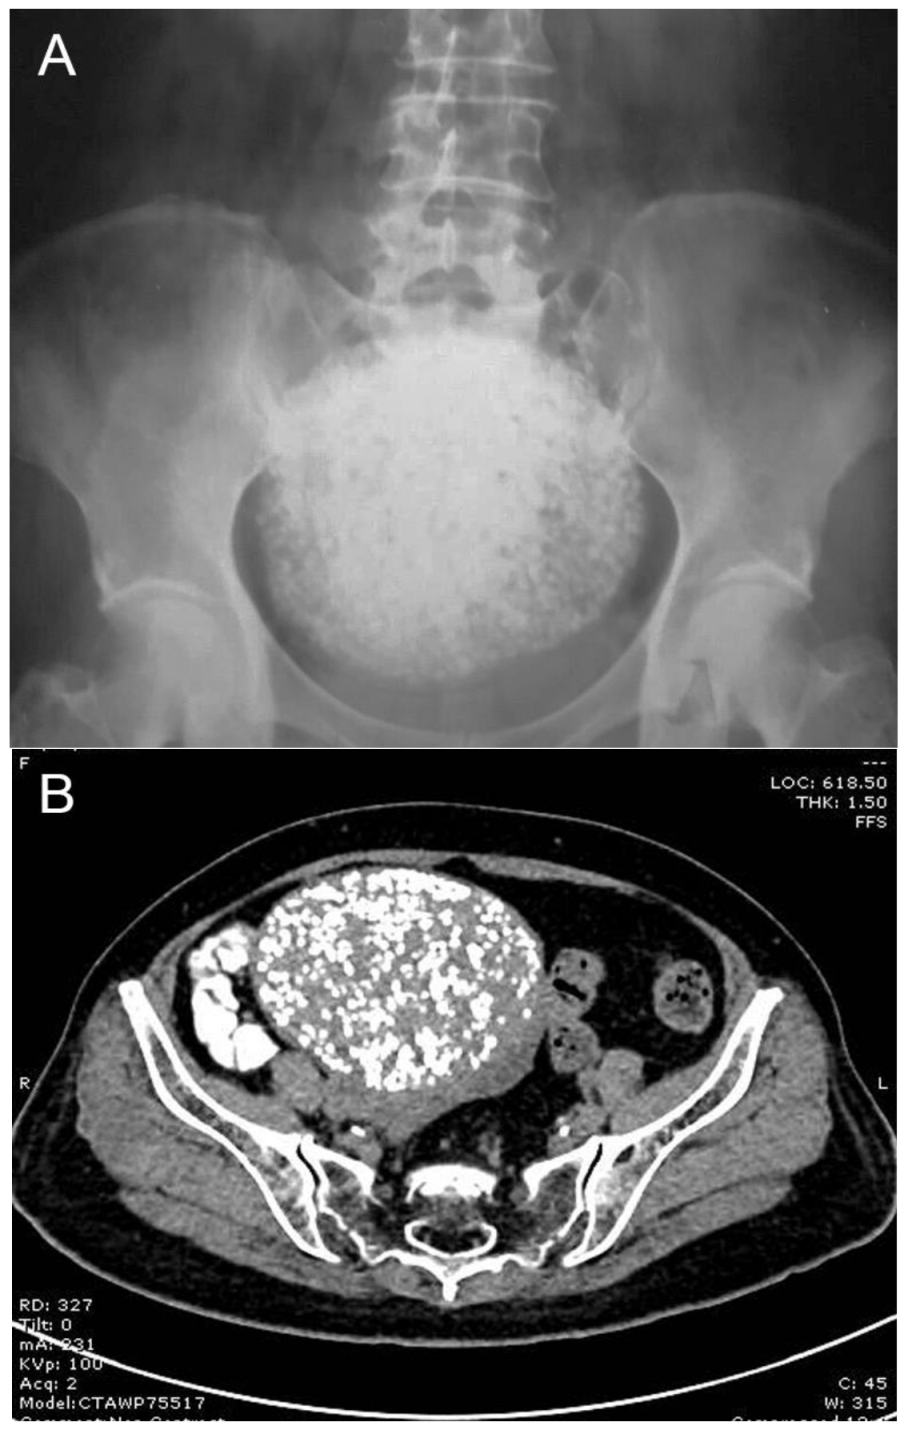

Figure 1. A 66-year-old nulliparous, postmenopausal Thai woman presented with lower back pain as well as pelvic discomfort for two weeks. Initial physical examination revealed a pelvic mass, no tenderness, a relatively smooth surface, firm consistency, and an estimated size of approximately 16–18 weeks of pregnancy. A plain film X-ray of the abdomen was performed to rule out orthopedic disorders because of low back pain symptoms. The X-ray findings showed a pelvic mass with severe calcification giving a scattered popcorn appearance, as presented in (A), whereas other bony structures were within normal limits. She was referred to our hospital for further management. Transabdominal ultrasound of the pelvis showed a mass with heavy acoustic shadow, resulting in non-informative details of the mass, and no vascularization. Because of the suboptimal ultrasound examination, a CT scan was performed and revealed an unusual pattern of popcorn appearance in the pelvis, as presented in (B). Severely calcified subserous leiomyoma uterus was a provisional diagnosis. The popcorn appearance on the cross-sectional plane of the CT scan of the pelvis (B) is much more clearly demonstrated than the AP plane of the film X-ray of the abdomen (A). Note that the mass was connected to the uterus. The mass measured 10.8 × 8.7 × 9.8 cm in diameter. The numerous small discrete calcified pellets were densely scattered all over the mass, giving the popcorn appearance, different from a homogeneous stony mass. The differential diagnoses of severely calcified mass may include ovarian teratoma, bladder calculi, calcified uterine leiomyoma, and bone tumors. A 3.7 × 2.9 cm right ovarian cyst was also noted. The left ovary appeared normal. The urinary bladder was compressed by an enlarged mass. No ascites and lymph node enlargement were seen.

Diagnostics 13 00154 g001